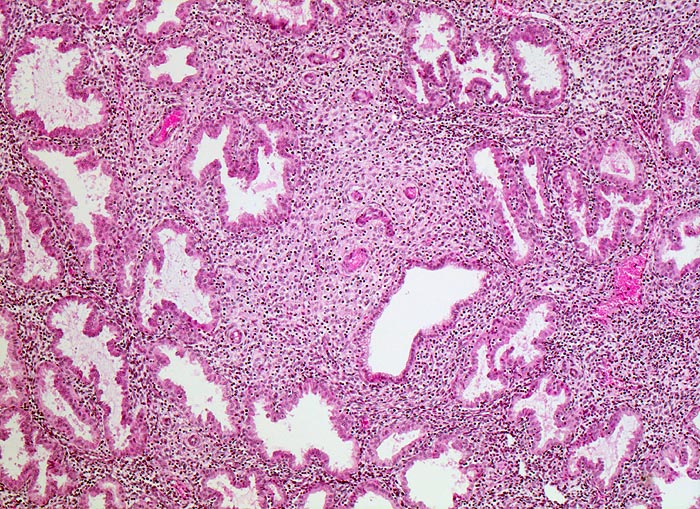

• Anstelle des Endometriums findet sich in der linken Hälfte des Uteruskavums ein Adenokarzinom bestehend aus architektonisch komplexen Drüsen. Die Drüsen liegen teils dos à dos ohne erkennbares Stroma zwischen zwei Drüsenschläuchen.

• Tumorzellverbände infiltrieren die glatte Muskulatur des Myometriums.

Endometrioide Karzinome bestehen aus tubulären Drüsen, welche von einem mehrreihigen Epithel ausgekleidet werden. Schleim ist meist nicht oder nur apikal in den Zellen vorhanden. Die Ausdehnung der soliden Areale und die zytologischen Atypien bestimmen den Differenzierungsgrad (low-grade versus high-grade). Metaplastisches Plattenepithel findet sich häufig in endometrioiden Karzinomen und hilft bei der Abgrenzung von anderen Subtypen. Das endometrioide Karzinom kann sich innerhalb von Adenomyoseherden im Myometrium entwickeln (> 4482). In diesen Fällen kann die Bestimmung der Infiltrationstiefe erschwert sein.